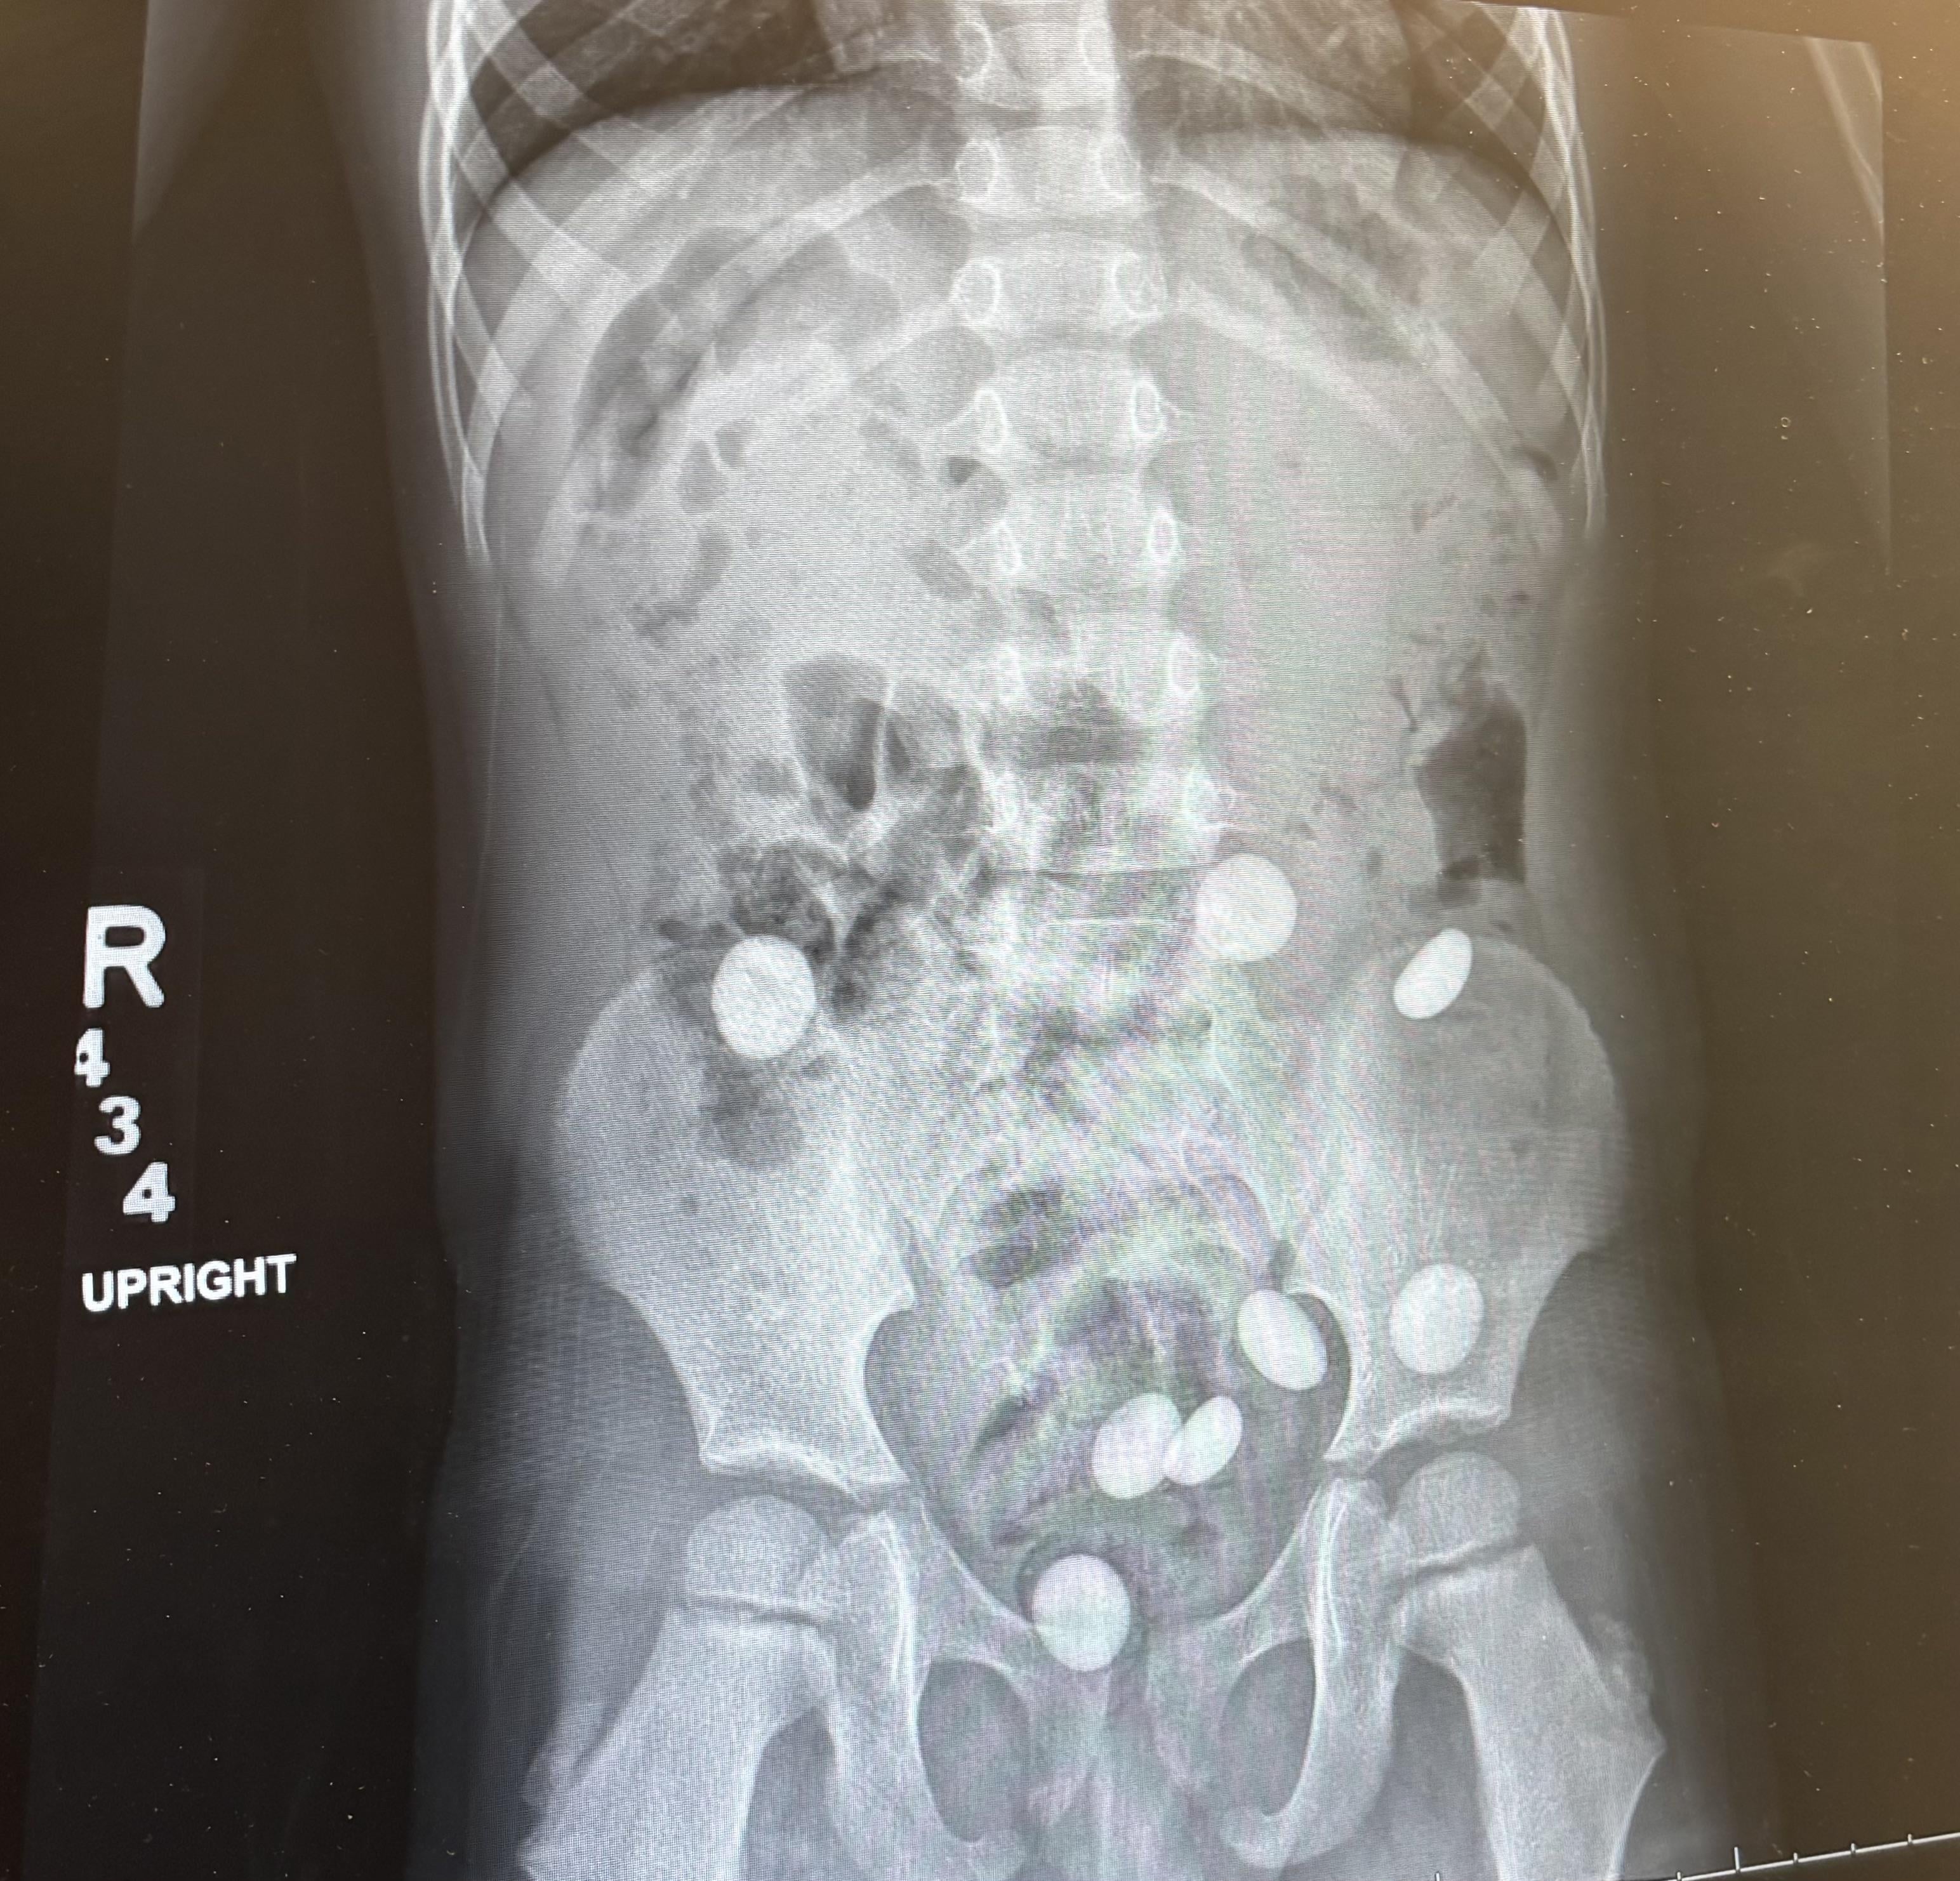

• My toddler swallowed 8 marbles

My toddler swallowed 8 marbles